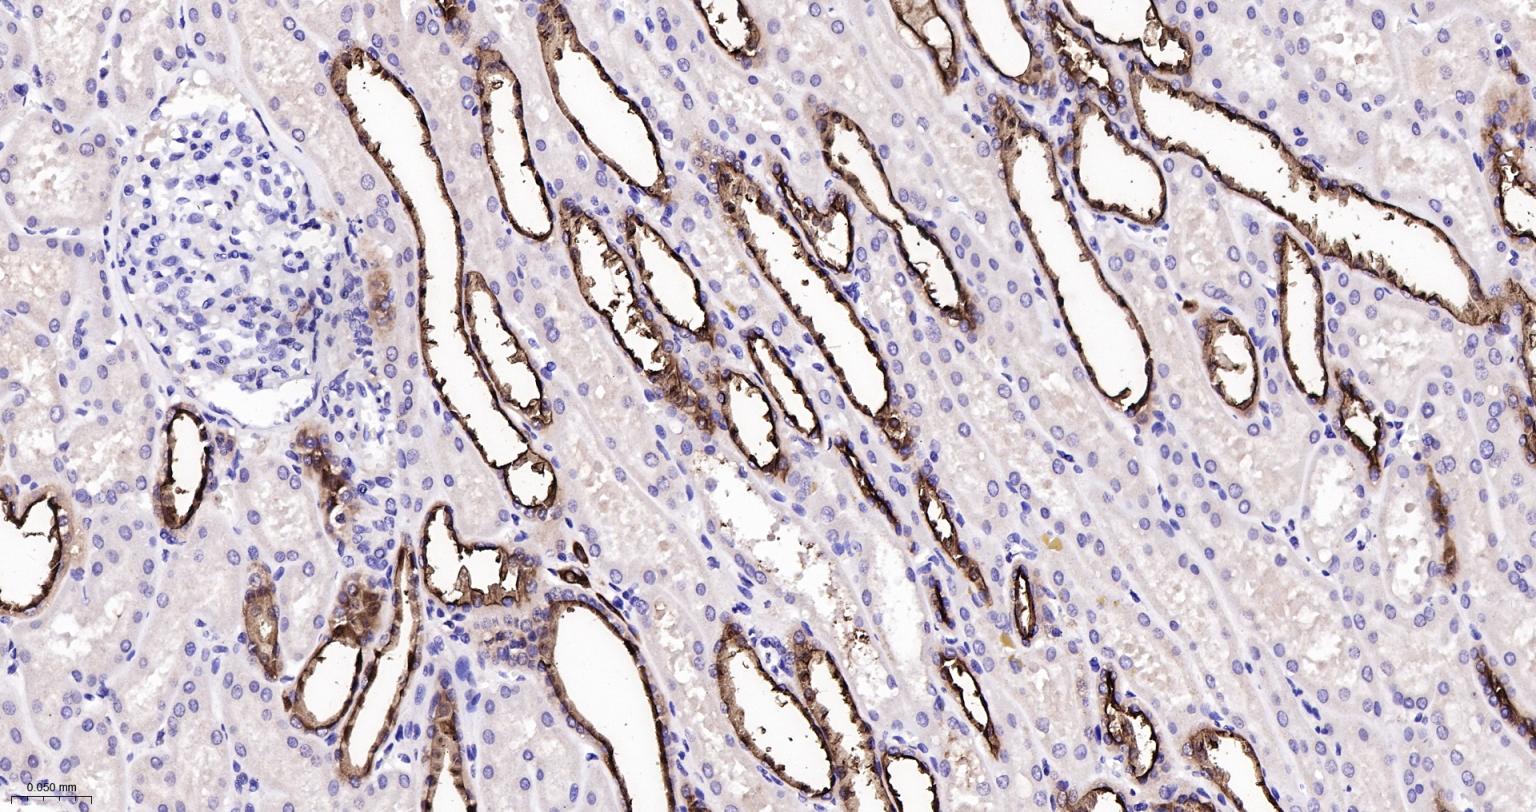

Paraformaldehyde-fixed, paraffin embedded Human Kidney; Antigen retrieval by boiling in sodium citrate buffer (pH6.0) for 15 min; Antibody incubation with MUC1 Monoclonal Antibody, Unconjugated(bsm-52576R) at 1:200 overnight at 4°C, followed by conjugation to the bs-0295G-HRP and DAB (C-0010) staining.